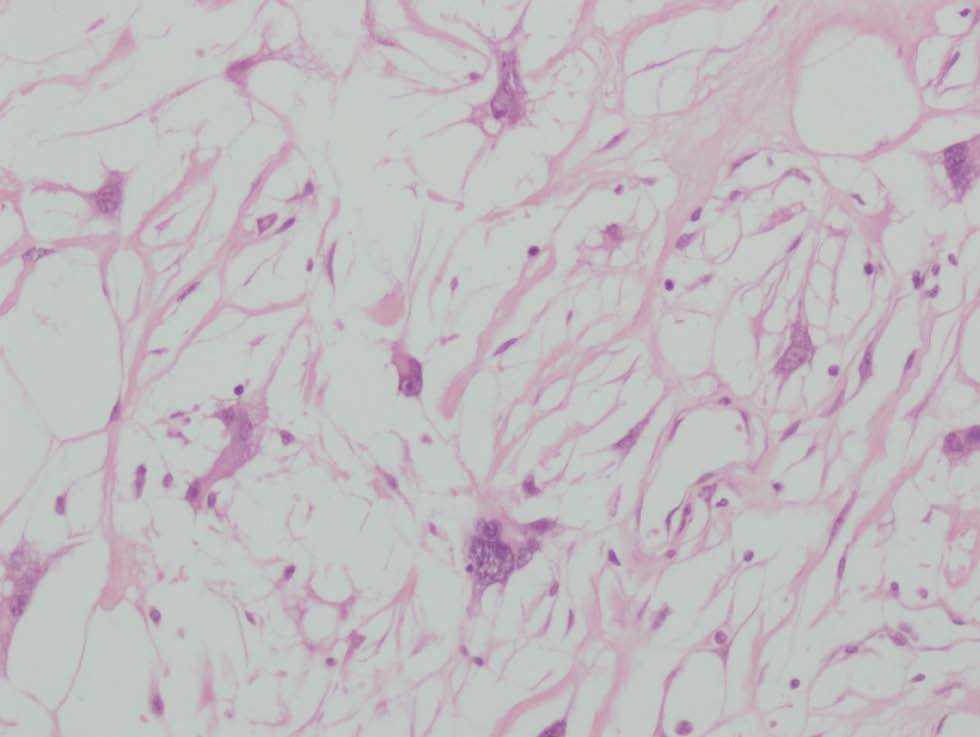

Histológicamente se observa una tumoración bien delimitada localizada en la dermis (fig. 1). El tumor muestra moderada cantidad de material mixoide entre tejido colágeno laxo. Entre las fibras de colágeno se observan células fusiformes, estrelladas y numerosas células gigantes multinucledas (fig. 2). Algunas de éstas tienen núcleos grandes, pleomórficos, hipercromáticos, con un pequeño nucleolo visible (fig. 3). Se observa escaso número de mitosis. La epidermis no muestra particularidades.

Fig. 3.--Células gigantes multinucleadas con núcleos grandes hipercromáticos (hematoxilina-eosina, 200).